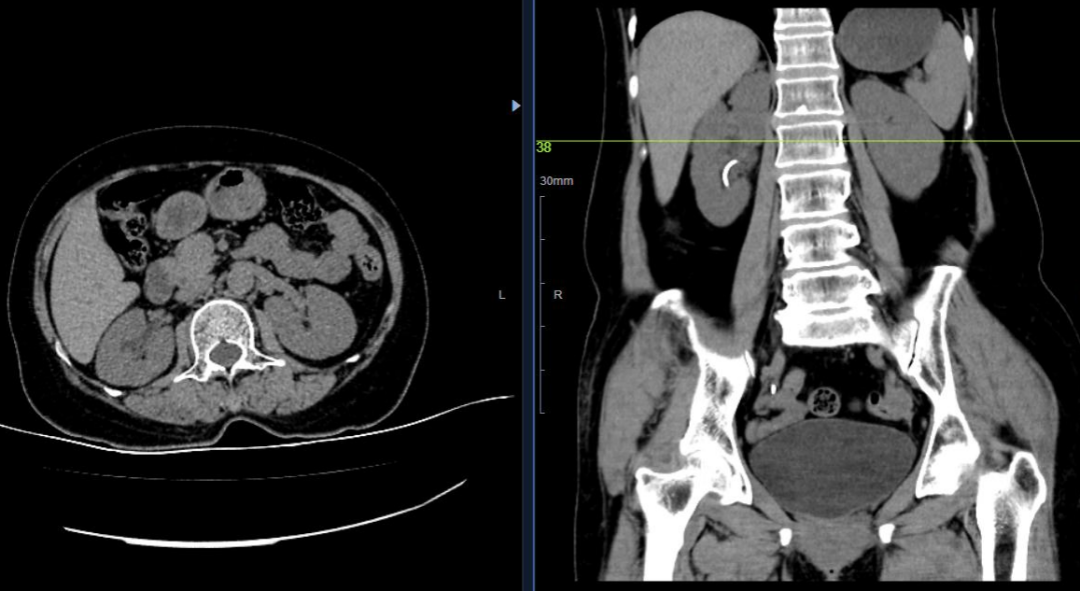

患者贾某,女性,年过六旬,因间断肉眼血尿住院。除血尿之外,并没有尿频、尿急等其他不适。间断性无痛性肉眼血尿首先应该考虑泌尿系统肿瘤,但患者泌尿系统影像学报告均未查见明显肿瘤特征,尿液脱落细胞学检查也未查见脱落的肿瘤细胞。为了进一步明确患者病情,科室特地邀请了原西安交通大学第一附属医院泌尿外科主任党建功教授来科查房并进行此病例讨论,经详细阅片及仔细研判,右侧肾盏内可见低密度影。并制定了进一步的诊查方案。

患者于2022年3月29日再次出现肉眼血尿,我科当机立断为患者行膀胱镜检查,术中见淡红色血性尿液自右侧输尿管口喷出。经过充分的术前准备,于2022年4月1日在全麻下行经尿道输尿管镜右侧肾盂肿物活检术,术中见右肾上盏内灰白色菜花样肿物,术后病检提示为肾盂移行上皮癌,根据病理报告结果,经科室讨论及准备,4月12日由张旭主任医师主刀,侯翔波、贾晓岳医师协助,在全麻下行腹腔镜右侧肾盂癌根治术,术中安全游离解剖显示下腔静脉,分别结扎肾动脉、肾静脉,完整剥离肾脏、腹膜后段输尿管,随后将肾脏完整取出,手术过程顺利。在护理团队的精心护理下,患者于术后第二天已可自行下床活动,手术后病理学检查提示肾盂原发移行上皮癌,已浸润输尿管上段,肾周脂肪囊、输尿管切缘未见癌细胞,经过科室全体医护人员精心照顾与护理,现患者已痊愈出院。感谢麻醉科、手术室科主任护士长及全体人员的保驾护航。此次后腹腔下肾盂癌根治术的成功完成是继2021年度完成后腹腔镜下肾癌根治术、输尿管癌根治术、保留肾单位等手术的又一大突破,同时也标志着我院泌尿外科又向前迈出了一大步。